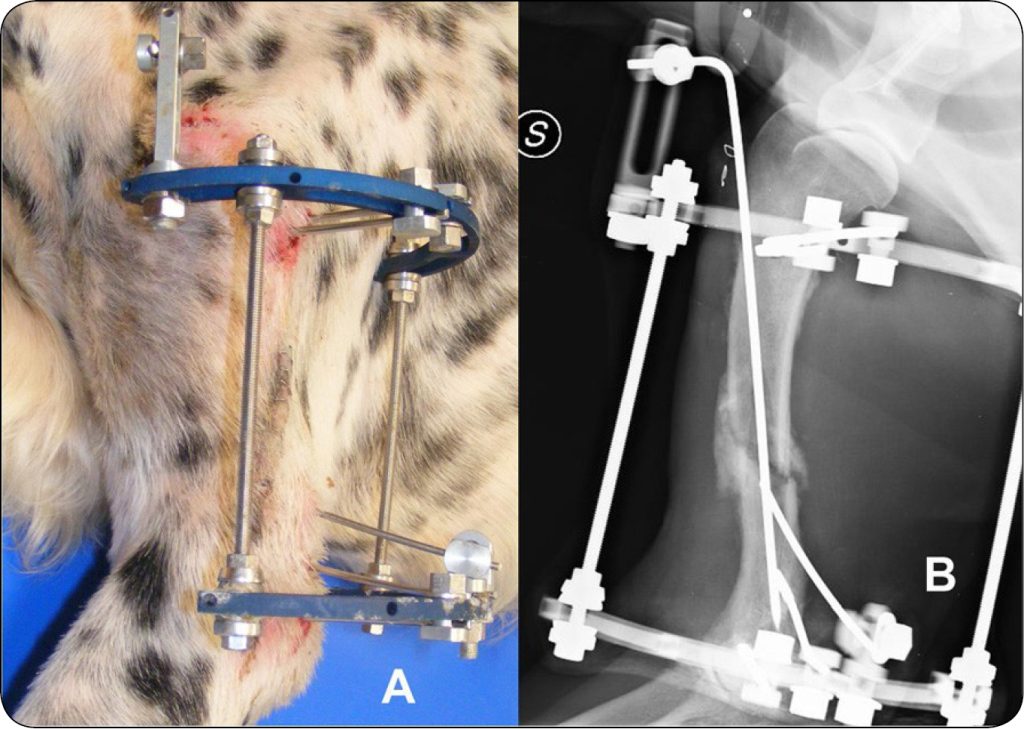

Sześć objętych badaniem przypadków stanowiły złamania kości ramiennej. Cztery z nich było wieloodłamowymi złamaniami trzonu kości, jedno było złamaniem spiralnym i jedno stawowym międzykłykciowym. W dwóch przypadkach zastosowano konfigurację IIB (ryc. 3), podczas gdy konfiguracje IA, IB, IC i IIIC zastosowano każdą w jednym przypadku. Konstrukcja ramy posiadała pierścienie 180° w czterech przypadkach, 270° w jednym i 360° też w jednym. W czterech ramach zastosowano fazowane elementy liniowe, a w dwóch ortogonalne. W żadnej z ram nie było konstrukcji rozporowej. W czterech przypadkach pojawiły się mniejsze powikłania. W żadnym z przypadków nie było poważnych powikłań. Czas gojenia dla złamań kości ramiennej wynosił 81,3 ± 23,6 dni (mediana: 71,5 dni, zakres: 60-120 dni).